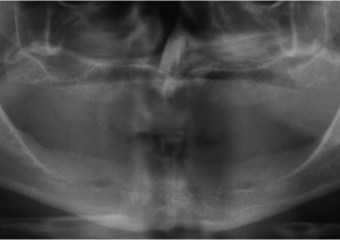

Rx do enxerto ósseo de maxila, com osso de crista ilíaca